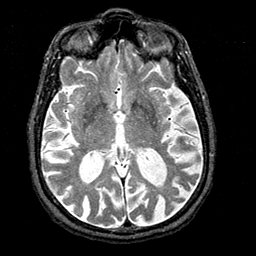

Alzheimer's disease MR T2-weighted -- Slice #24

Tour 1: Next/Previous/Start: The third ventricle is enlarged and contains a barely visible massa intermedia.